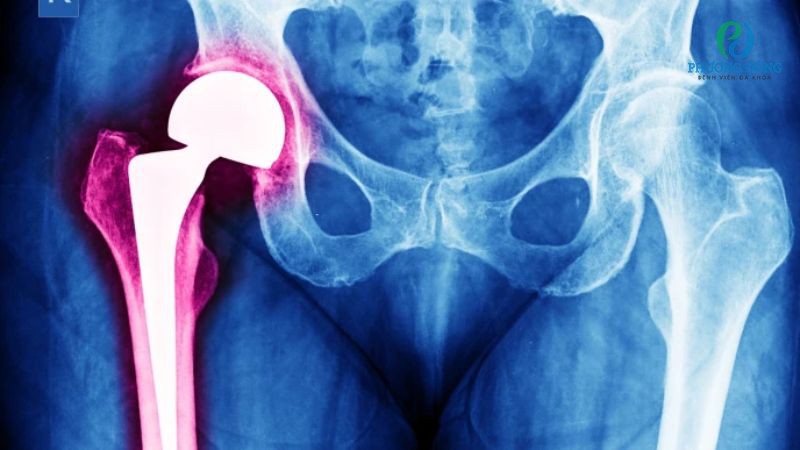

Nhiễm trùng sau thay khớp háng nhân tạo là gì?

Nhiễm trùng sau thay khớp háng nhân tạo là tình trạng vi khuẩn xâm nhập vùng quanh khớp nhân tạo, gây phản ứng viêm nhiễm. Đây được xác định là biến chứng hậu phẫu nguy hiểm, cần được nhận diện và can thiệp xử trí sớm.

Nhiễm trùng sau thay khớp háng nhân tạo là một trong những biến chứng nguy hiểm